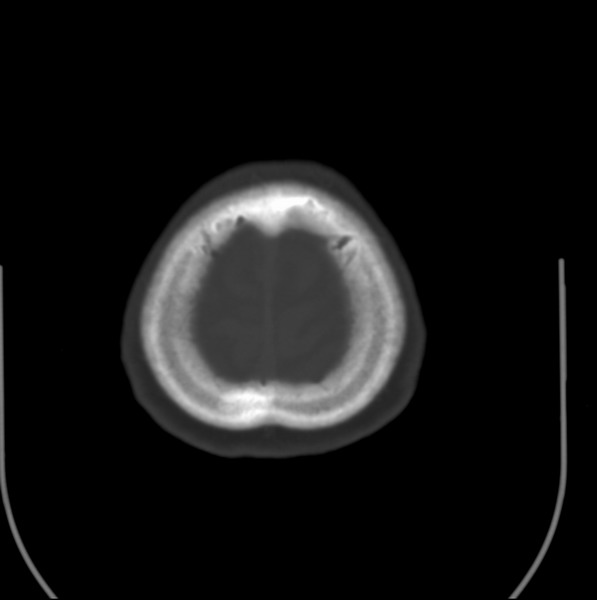

以下是引用余辉在2009-4-25 10:34:00的发言:[br]上矢状窦旁软组织肿块,内有钙化,与上矢状窦边界不清,灶后颅骨内板骨质增生硬化,支持考虑脑膜瘤,建议增强

以下是引用hmyj9在2009-4-25 14:21:00的发言:[br]病灶紧贴颅板处,中心高密度周围见软组织密度,局部颅板有增生,支持脑膜瘤诊断,建议增强。

以下是引用边生丽在2009-4-25 11:55:00的发言:[br][br] [br] 考虑脑膜瘤可能性大;建议行进一步检查。 [br] [br] [br]